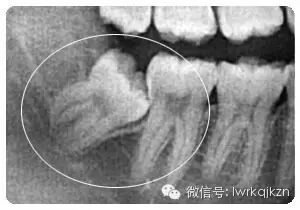

二、影响邻牙:如果生长空间不足,智齿会使劲儿顶住相邻的牙齿继续生长,可能导致邻牙损伤最后两颗牙齿都保不住。

六、阻生齿:这种类型的智齿,通常埋在齿槽骨的里面,当你感觉到痛时,就要拔掉它。

得了智齿,忍忍就过了,你这样想可就错了,如果智齿不加以重视,可能就是这看似不起眼的小麻烦,让你痛苦万分,智齿的最大危害就是极其容易造成食物嵌塞,由于智齿不能完整地萌出在正常位置,因此与前面的牙齿不能形成良好的接触关系,那么就容易有食物残渣、细菌等滞留于智齿与其前面相邻牙齿之间的间隙中,这样容易造成智齿前面邻牙的龋坏,然后可能发展为牙髓炎。

另外,这一部位的牙槽骨也容易吸收,导致智齿前面的牙齿松动。不能完全萌出的智齿,非常容易发生智齿冠周炎,在疲惫,身体抵抗力低下的时候容易发作,智齿冠周炎有可能反复发作,如果治疗不积极的话,有可能形成口腔颌面间隙的感染。